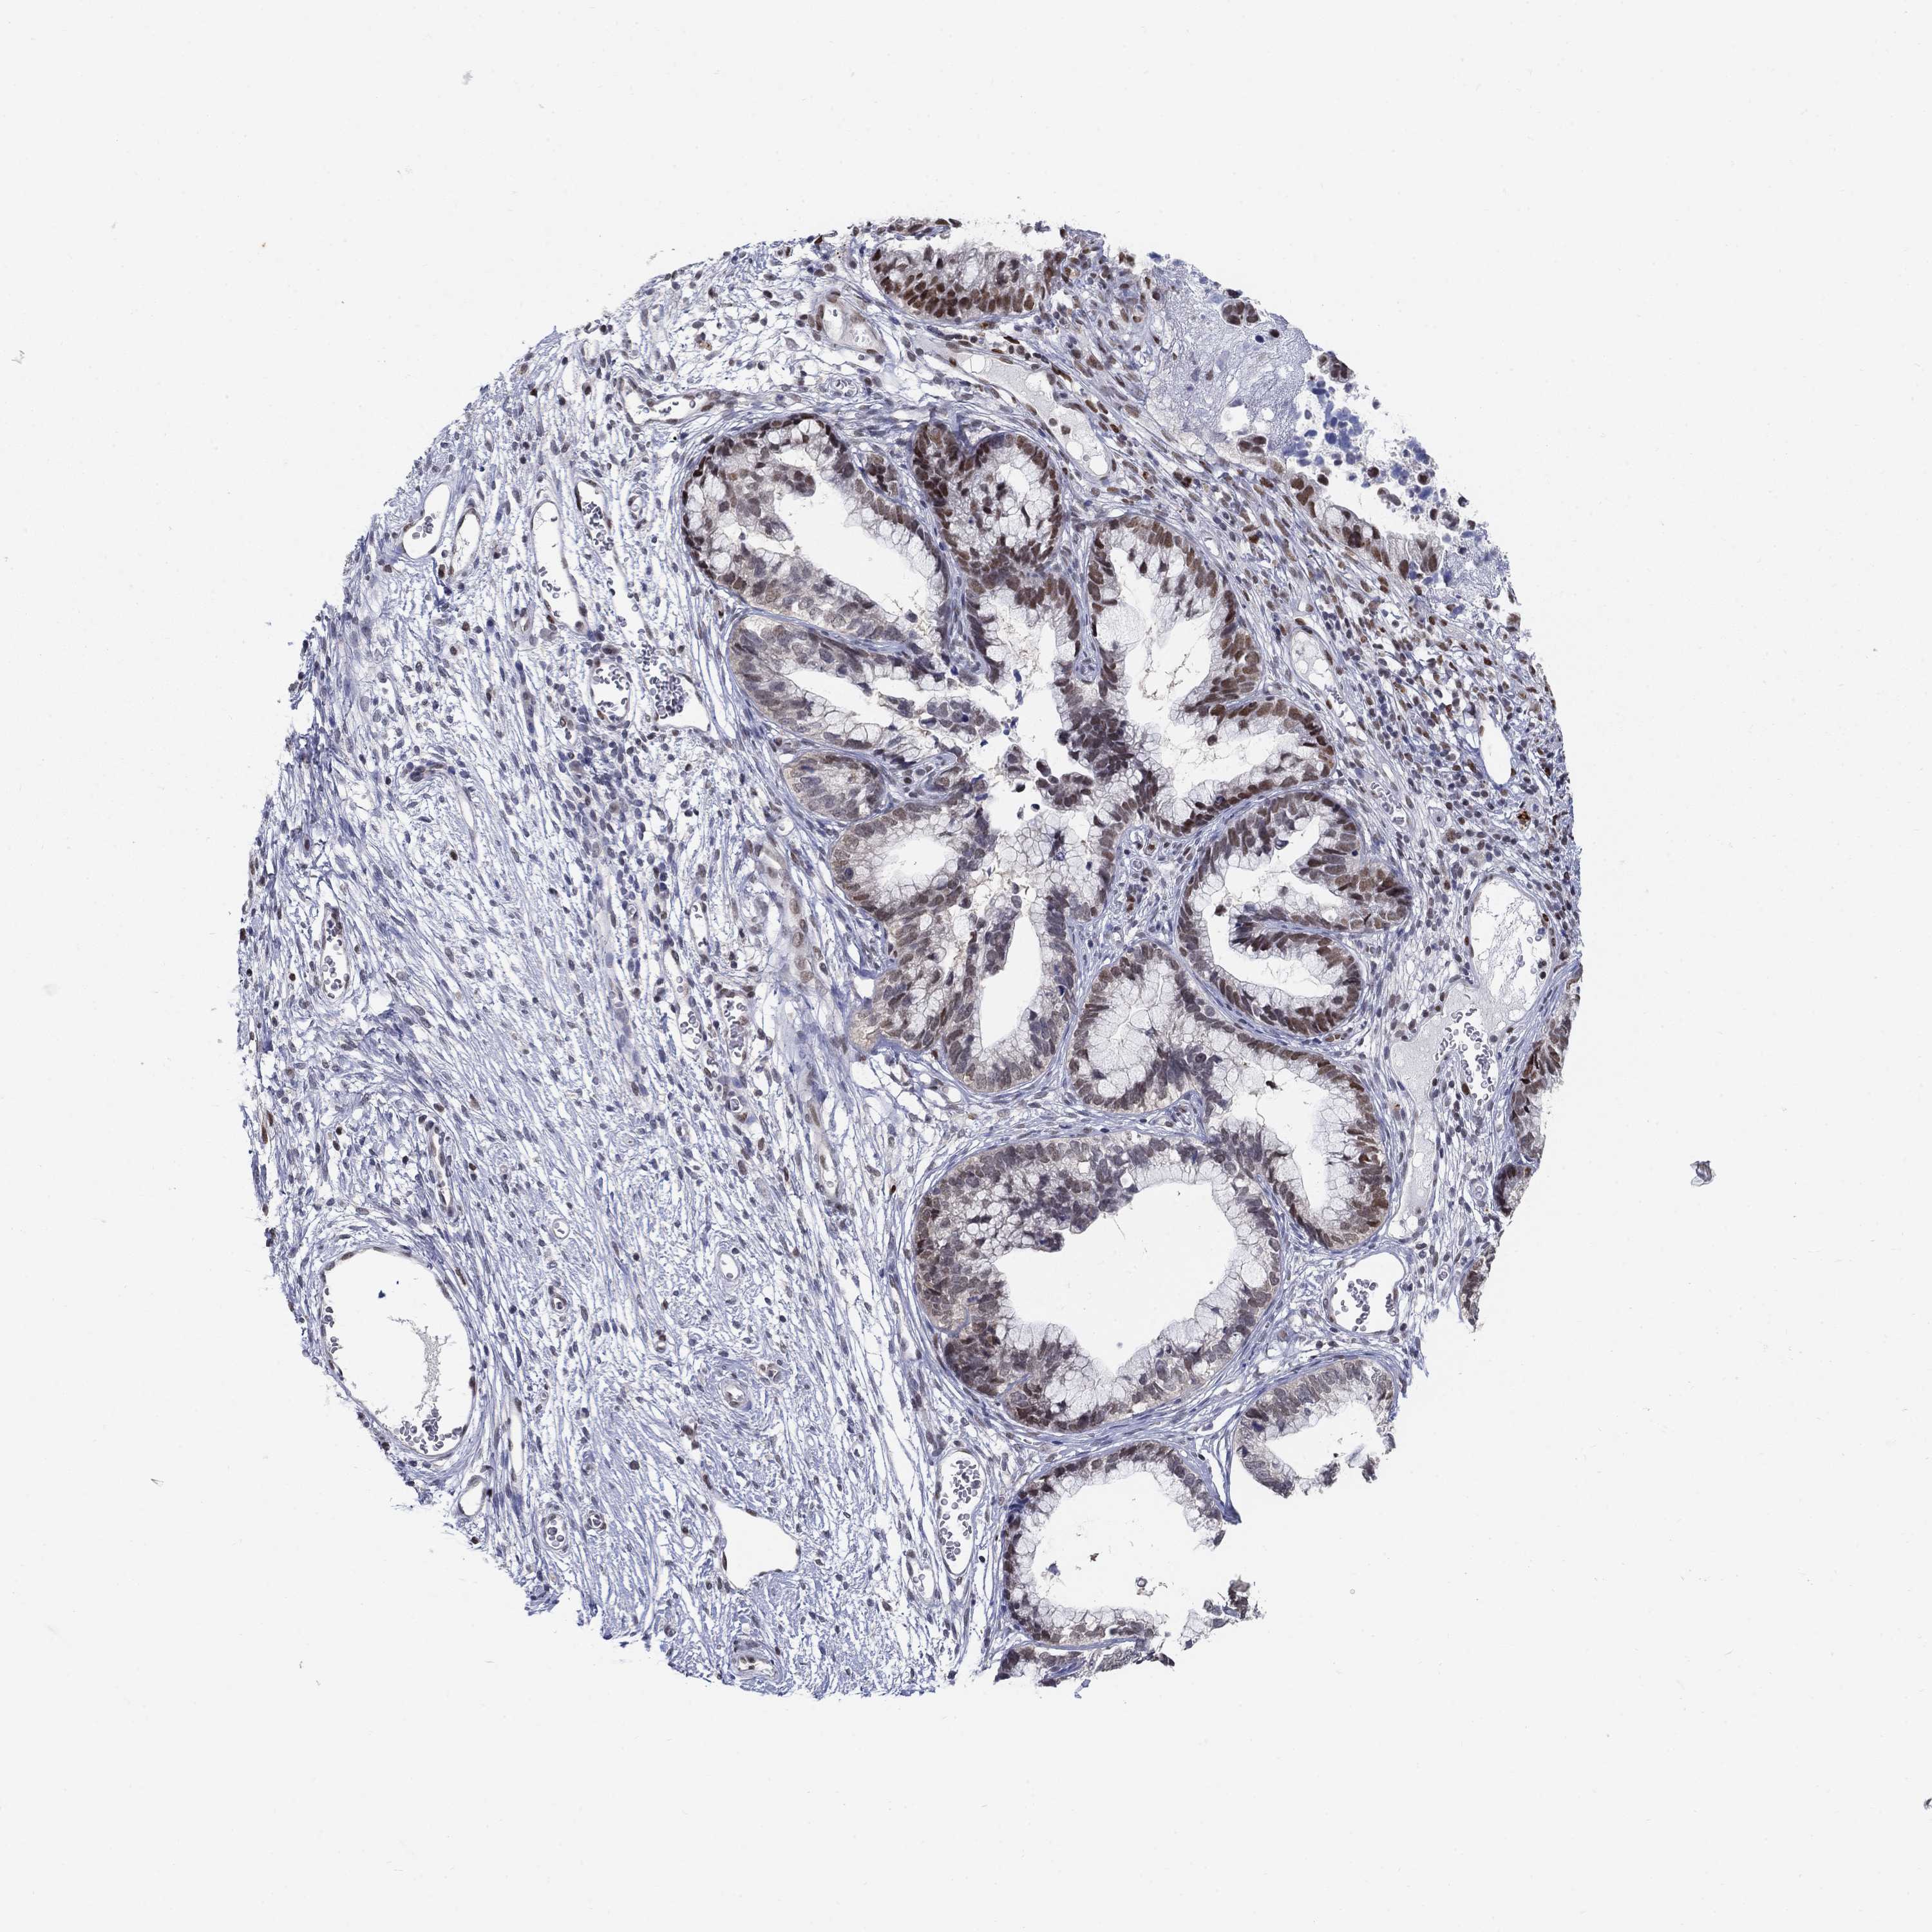

CERVICAL CANCER - Protein expressioni

A mouse-over function shows sample information and annotation data. Click on an image to view it in a full screen mode. Samples can be filtered based on level of antibody staining by selecting one or several of the following categories: high, medium, low and not detected. The assay and annotation is described here.

Note that samples used for immunohistochemistry by the Human Protein Atlas do not correspond to samples in the TCGA dataset.

Antibody stainingi

Antibody staining in the annotated cell types in the current human tissue is reported as not detected, low, medium, or high, based on conventional immunohistochemistry profiling in selected tissues. This score is based on the combination of the staining intensity and fraction of stained cells.

Each image is clickable and will lead to virtual microscopy that enables deeper exploration of all samples and also displays staining intensity scores, fraction scores and subcellular localization as well as patient and tissue information for each sample.

Antibody HPA042294

Staining

High

Medium

Low

Not detected

Intensity

Strong

Moderate

Weak

Negative

Quantity

>75%

75%-25%

<25%

None

Location

Nuclear

Cytoplasmic/membranous

Cytoplasmic/membranous,nuclear

Squamous cell carcinoma, NOS

Adenocarcinoma, NOS